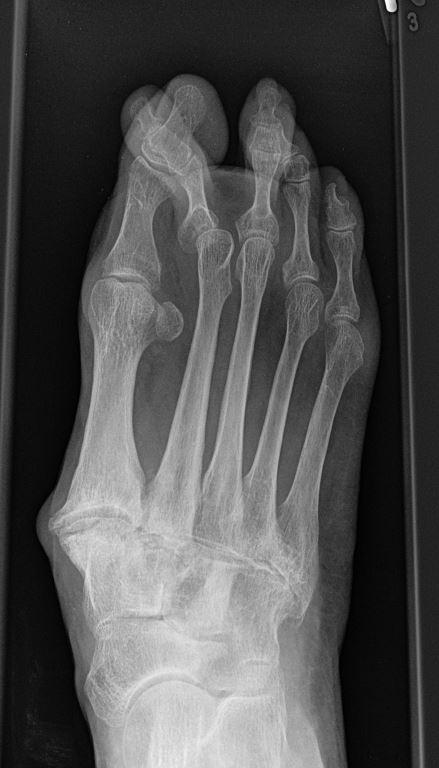

Häufig werden die Arthrosen der Lisfranc-Gelenklinie relativ spät diagnostiziert. Die Gründe dafür liegen oft daran, dass die Patienten selbst einen Schmerz an der Fußwurzel nicht mit dem Symptomkomplex Spreizfuß und Hallux valgus in Verbindung bringen. Auch werden in der Primärdiagnostik häufig nur vom Vorfuß Röntgenbilder angefertigt oder die angewandte Röntgentechnik erlaubt keine Einsicht in die Lisfranc-Gelenklinie.

Eine Röntgenaufnahme unter Belastung mit Abbildungen des ganzen Fußes a. p. (mit 15-20° Röhrenkippung) und seitlich, sowie Schrägaufnahmen, reichen meist zur Diagnose. Manchmal ist ein MRT und DVT ergänzend hilfreich. Selten wird die Indikation für ein SPECT CT gestellt (Abb. 6).

• konventionelle Röntgenbilder mit Belastung im Stehen a. p. und seitlich, ggf. schräg (Abb. 9, 10 und 11).